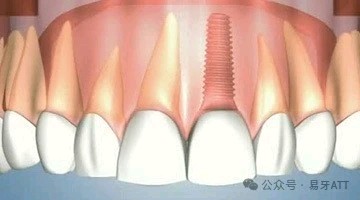

与种植牙相比:能达到生活牙齿的所有性能,有些牙齿移植后可达到牙髓愈合,有本体感受器存在,能感受冷热等刺激并加以保护。适应年龄放宽,即18岁以下也能适用。